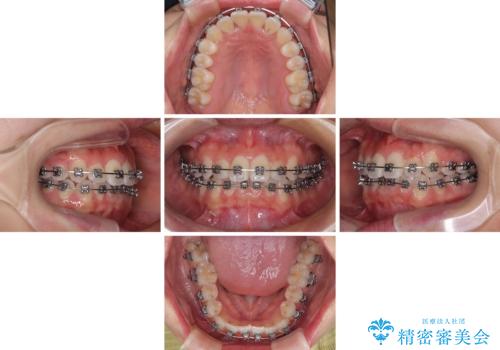

前歯のクロスバイト 裏側に隠れた歯をワイヤー装置で短期間治療

- 矯正装置

- メタルブラケット

- 治療期間

- 1年2ヶ月

- 上顎前歯のクロスバイトを気にして来院された患者様です。

ワイヤー矯正でもマウスピース矯正でも対応可能でしたが、マウスピースによる自己管理に一切の自信がないとのことで、ワイヤー装置にて矯正治療を行うこととしました。

装置の外見を気にしていましたが、短期間で治療を終えることができるだろうと伝えると、安価であるメタルブラケットを選択されました。

想定通り、1年強で綺麗に仕上げることができました。